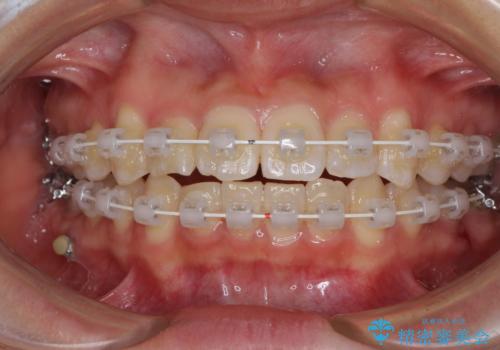

- 審美装置

- 1年

- 10-30回

お住まいが遠方であったため、マウスピースによる矯正治療も提案しましたが、ご自身でのマウスピースの管理の面倒くささと、なるべく早く治療を終えたいとのことで、ワイヤー矯正を選択されました。